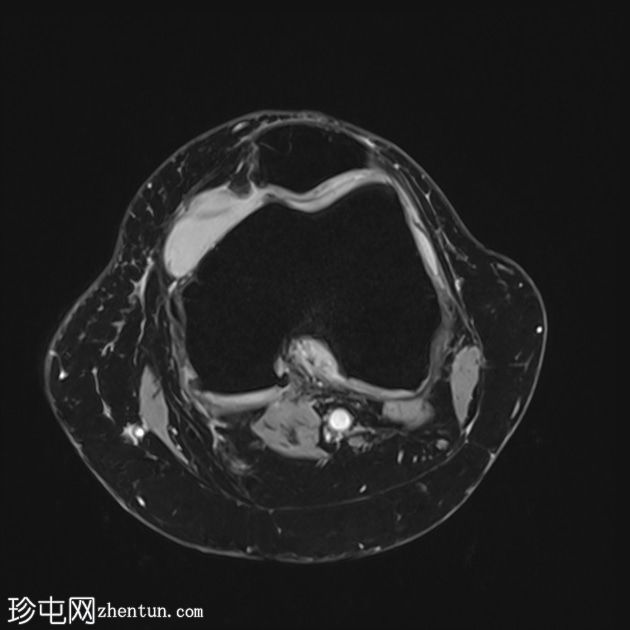

矢状位质子密度加权像 (PD)

脂肪抑制像

前交叉韧带 (ACL) 呈增厚的高信号,提示黏液样变性。然而,纤维仍保持连续性,在矢状位质子密度加权像上尤为明显。这种特征性表现类似于芹菜,因此被称为“芹菜茎征”。

内侧半月板后角显示异常信号,延伸至关节面下方,符合3级撕裂。

髌股关节和胫股关节均可见骨关节炎改变,表现为骨赘形成、胫骨棘突增生以及关节软骨在相对关节面上的剥脱。

可见少量滑液积液,滑液内可见髌上皱襞。

该病例的特征为前交叉韧带黏液样变性。此外,还有退行性关节病伴轻度关节积液,以及髌上皱襞撕裂和内侧副韧带扭伤。